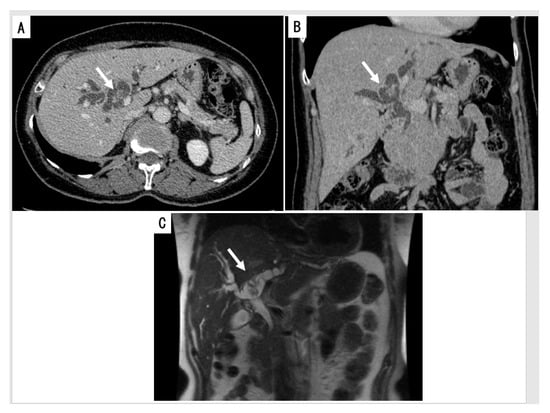

2.2.2. Cholangiography

- Tsuyuguchi, T.; Sakai, Y.; Sugiyama, H.; Miyakawa, K.; Ishihara, T.; Ohtsuka, M.; Miyazaki, M.; Yokosuka, O. Endoscopic diagnosis of intraductal papillary mucinous neoplasm of the bile duct. Hepatobiliary Pancreat Sci. 2010, 17, 230–235. [Google Scholar] [CrossRef]

- Yeh, T.S.; Tseng, J.H.; Chiu, C.T.; Liu, N.J.; Chen, T.C.; Jan, Y.Y.; Chen, M.F. Cholangiographic spectrum of intraductal papillary mucinous neoplasm of the bile ducts. Ann. Surg. 2006, 244, 248–253. [Google Scholar] [CrossRef] [PubMed]

- Tsou, Y.K.; Liu, N.J.; Wu, R.C.; Lee, C.S.; Tang, J.H.; Hung, C.F.; Jan, Y.Y. Endoscopic retrograde cholangiography in the diagnosis and treatment of mucobilia. Scand J. Gastroenterol. 2008, 43, 1137–1144. [Google Scholar] [CrossRef] [PubMed]